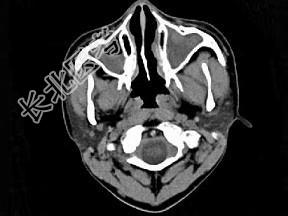

- 单项选择题男,14岁, 持续性鼻塞、嗅觉减退,流脓涕数年, CT检查如图,最可能的诊断为 ( )

A、鼻炎及鼻窦炎

B、鼻及鼻窦息肉

C、过敏性鼻炎及鼻窦炎

D、恶性肉芽肿

E、上颌窦癌